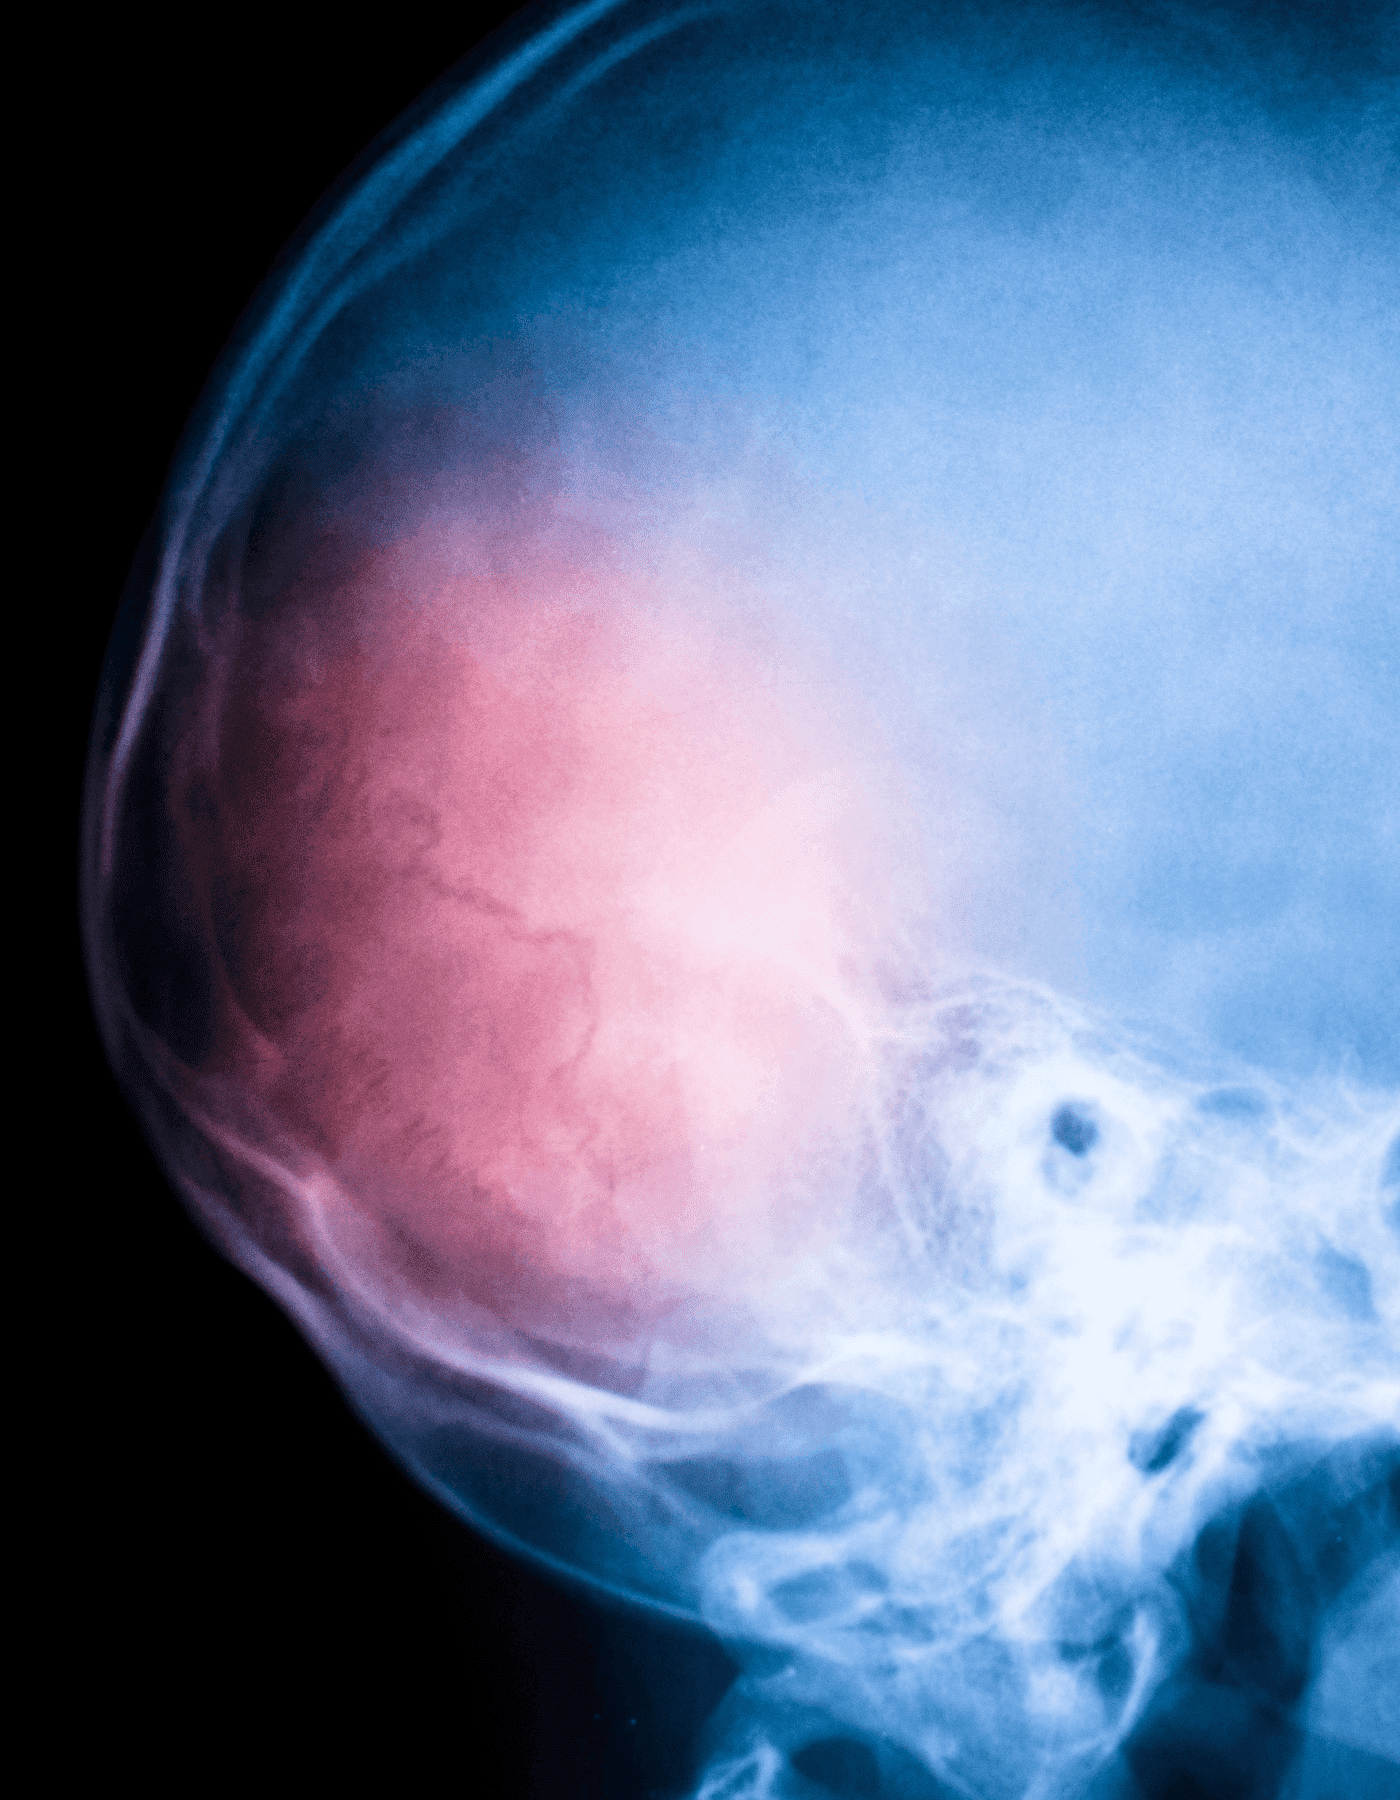

Craneotomía y Drenaje